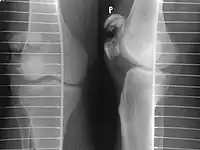

A fracture of the patella seen on a lateral view